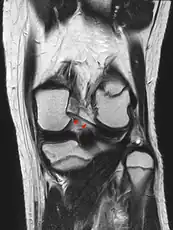

Posterior meniscofemoral ligament on MRI, sagittal